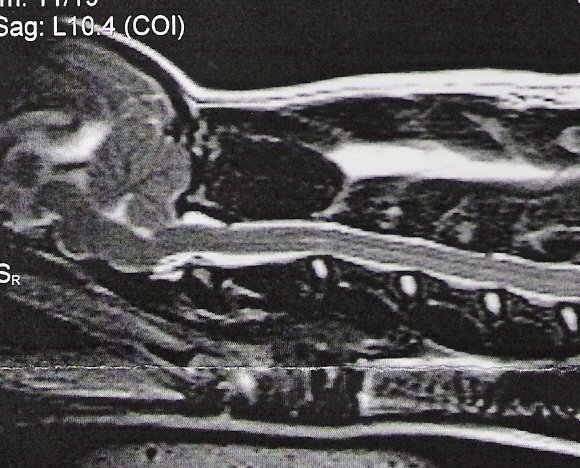

Above is shown a comparison of an MRI showing a full cerebellum

vs. the skull X-RAY of a dog with a full cerebellum and a dog

with an MRI showing a crushed cerebellum vs. the skull X-RAY of

a dog with a crushed cerebellum. The cerebellum is circled in

red. You can easily see there is a huge difference in shape of

cerebellum between these two dogs--the one on the left is quite

full, the one on the right is severely crushed.